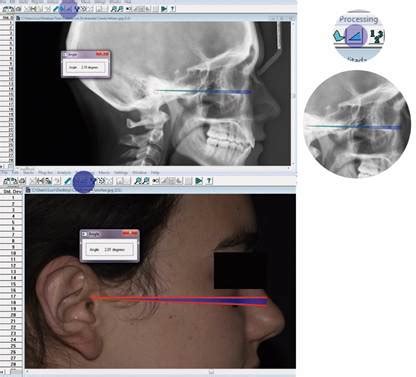

Posición natural de la cabeza

Cole definió la posición natural de la cabeza (natural head position, NHP) como la relación de la cabeza con respecto a la vertical verdadera, y la postura natural de la cabeza como la relación entre la cabeza y las vértebras cervicales. En tanto que magnitud reproducible, posibilita comparaciones racionales entre diversos estadios de tratamiento en el mismo paciente y comparaciones cefalométricas racionales entre pacientes.

La posición natural de la cabeza se establece ya en etapas tempranas de la vida. Se ve influida por los requisitos del equilibrio (conductos del oído medio vestibulares) y de la capacidad visual (eje facial horizontal), así como por la propiocepción de las articulaciones y la musculatura en postura erguida. Es más constante en comparación con otras líneas de referencia dentro del cráneo. Las evaluaciones de perfiles en telerradiografías laterales pueden alcanzar un alto grado de precisión si se mantiene la cabeza en su posición natural y se registra la cantidad suficiente de datos de tejidos blandos.

Los autores utilizan la posición natural de la cabeza como ayuda orientativa durante evaluaciones fotográficas de proporciones faciales, así como para la realización y la evaluación de radiografías cefalométricas. A fin de determinar la posición natural de la cabeza, se pide al paciente sentado que mantenga la cabeza recta y mire un espejo situado directamente delante, con los pies ligeramente separados y los brazos colgando. Tanto los labios como la musculatura maxilar y de la nuca deberían estar relajados.

A fin de determinar la posición natural de la cabeza, se pide al paciente sentado que mantenga la cabeza recta y mire un espejo situado directamente delante, con los pies ligeramente separados y los brazos colgando. Tanto los labios como la musculatura maxilar y de la nuca deberían estar relajados.